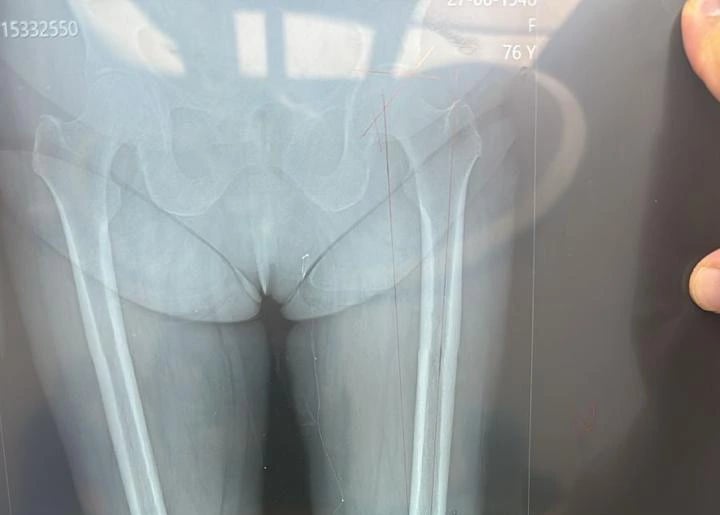

- Fracturas

- Fractura de Fémur